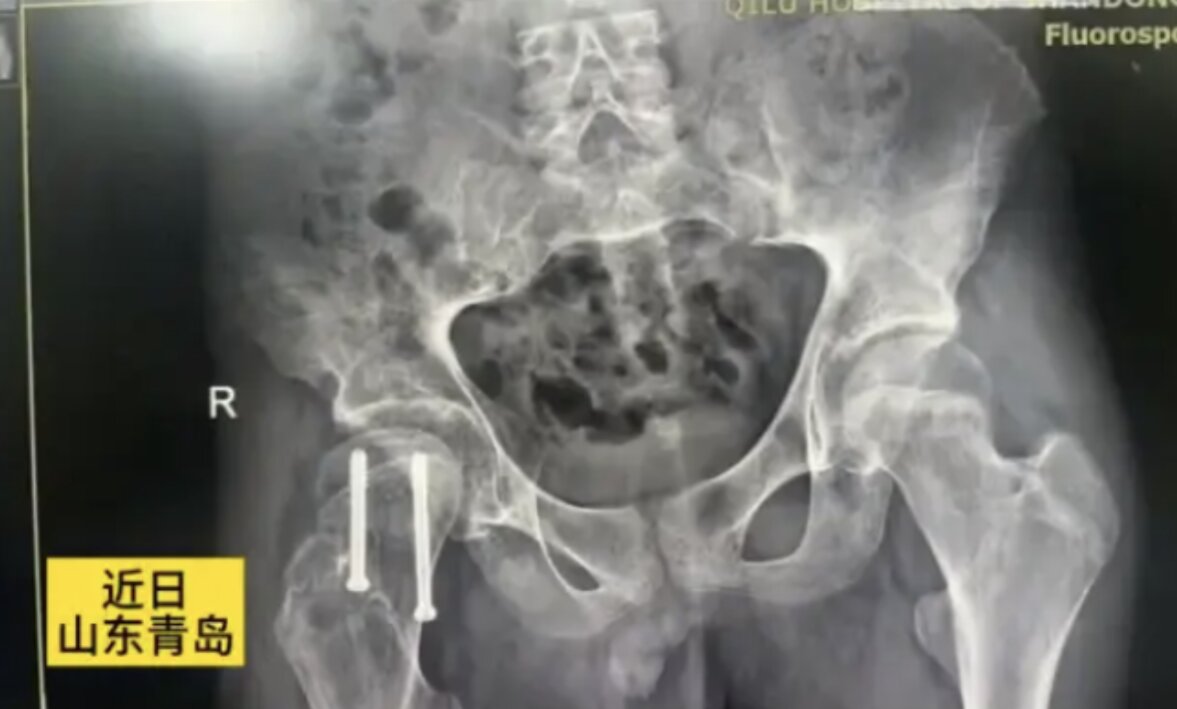

Bên cạnh hội chứng đứt cuống tuyến yên, anh Ai còn mắc chứng trượt đầu xương đùi, một bệnh thường gặp ở thanh thiếu niên. Chứng bệnh này làm tình trạng sức khỏe của anh thêm phức tạp, gây đau đớn và hạn chế vận động.

Trượt đầu trên xương đùi (SCFE) là một tình trạng thường gặp ở vùng hông, chủ yếu xuất hiện ở thanh thiếu niên và thanh niên trong giai đoạn phát triển thể chất. Ở bệnh lý này, cổ xương đùi bị trượt lệch khỏi vị trí bình thường trên đầu xương đùi, hướng lên trên và ra trước, gây đau đớn, cứng khớp và làm suy giảm độ ổn định của khớp háng. Tình trạng này thường tiến triển từ từ và có tỷ lệ mắc ở nam giới cao hơn so với nữ.

May mắn thay, anh Ai đã được phẫu thuật đóng đinh nội tủy rỗng để điều trị chứng trượt đầu xương đùi bên phải. Ca phẫu thuật đã thành công, giúp giảm đau đáng kể và cải thiện khả năng vận động cho anh. Tiên lượng sau phẫu thuật của anh được đánh giá là tốt.